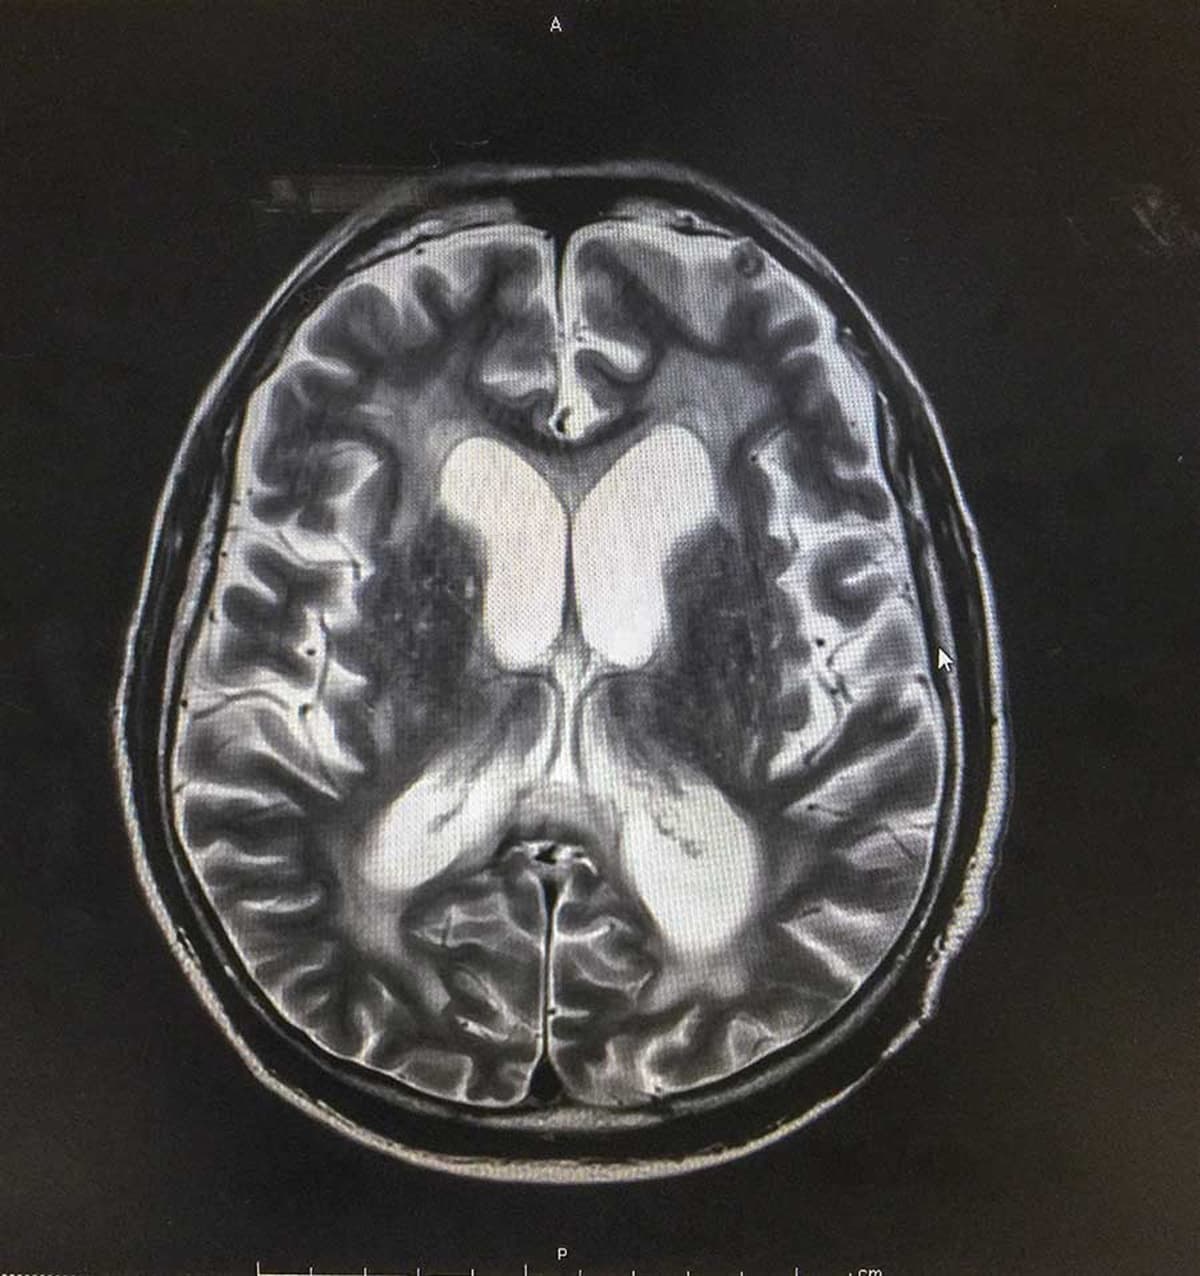

Hidrosefali, beyin omurilik sıvısının miktar ve basıncının artışı ile oluşan bir hastalıktır. Anne karnında bulunan ve yenidoğan bebekler de dahil olmak üzere her yaşta görülebilen hidrosefali, sıvı birikiminin beyin üzerinde baskı yapması nedeniyle çok sayıda soruna neden olabilmektedir. Beyinde gelişen hasarlar çocuk ve yetişkinlerde birtakım zihinsel ve fiziksel problem ortaya çıkarmaktadır.

Operasyon, 1-2 cm uzunluğundaki bir cilt kesisi açılarak yapılmaktadır. Kafatasına açılan 8 mm genişliğindeki bir delikten endoskop (ışıklı kamera) ile üçüncü karıncığa ulaşılmaktadır. Bu karıncığın alt bölümü beyincik ve omurilik sıvısının dolaşım kanallarından birini oluşturmaktadır. Bu bölgenin tıkanması beyin ya da omurilik sıvısının akışkanlığını engelleyerek sıvının burada toplanmasına neden olmaktadır. Endoskopik yöntem tıkanıklığın açılarak ya da yeni bir yol oluşturularak biriken sıvının akıtılmasını sağlamaktadır.